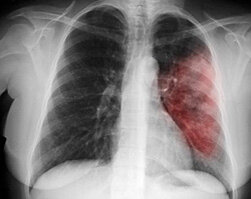

Как долго нужно пить антибиотики при пневмонии?